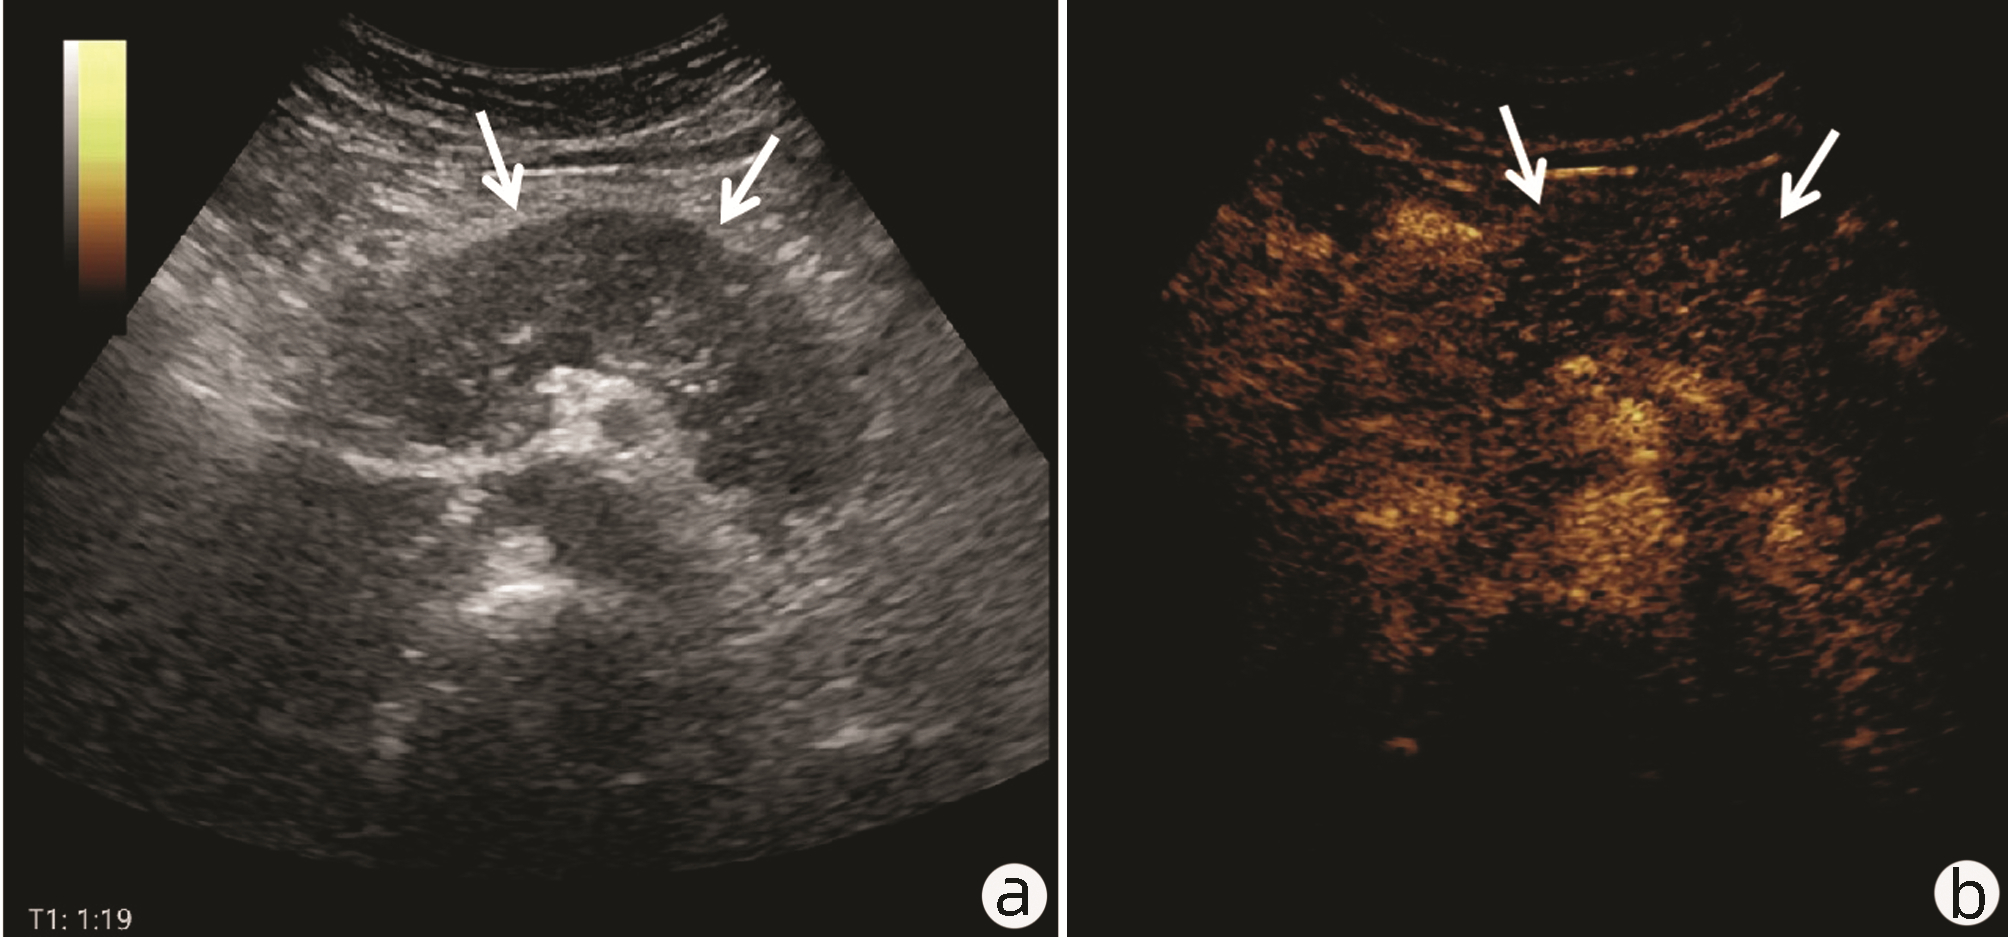

Value of 18F-FDG PET/CT, contrast-enhanced ultrasound, and their combined use in differential diagnosis of benign and malignant pancreatic lesions: A comparative study

Lichun ZHENG, Xiaoming ZHANG, Tianying YU, Jie LI, Xiaoqian DENG, Xiangliu OUYANG

2022, 38(12): 2774-2779. DOI: 10.3969/j.issn.1001-5256.2022.12.017

Abstract(2246) HTML (1599) PDF (3391KB)(53)

Abstract:

Objective  To assess the value of 18F-FDG PET/CT, contrast-enhanced ultrasound, and their combination in the differential diagnosis of benign and malignant pancreatic lesions.  Methods  A retrospective analysis was performed on patients with pancreatic lesions who underwent18F-FDG PET/CT and contrast-enhanced ultrasound who were admitted to Tangshan Gongren Hospital from January 2015 to December 2020. The imaging results were confirmed by pathology examination to evaluate diagnostic sensitivity, specificity, accuracy, positive and negative predictive value. The t-test was used for comparison of continuous data between two groups, and the chi-square test was used for comparison of categorical data between groups.  Results  There were 83 malignant lesions and 25 benign lesions in 108 patients. The sensitivity, specificity, accuracy, positive and negative predictive value were 86.75%, 80.00%, 85.19%, 93.51% and 64.52% for 18F-FDG PET/CT; and 69.88%, 76.00%, 71.30%, 90.63% and 43.18% for contrast-enhanced ultrasound, respectively. The two methods differed significantly in sensitivity and accuracy (all P < 0.05), but not in specificity, negative and positive predictive value (all P > 0.05). When combined with the contrast-enhanced ultrasound, 18F-FDG PET/CT had an increased sensitivity, specificity, accuracy, positive and negative predictive value of 90.36%, 84.00%, 88.89%, 94.94% and 72.41%, respectively, though this was not statistically significant due to the increased signal of blood supply in the lesions.  Conclusion  18F-FDG PET/CT has a better performance than contrast-enhanced ultrasound in the differential diagnosis of benign and malignant pancreatic lesions, and their combination can improve the diagnostic value.